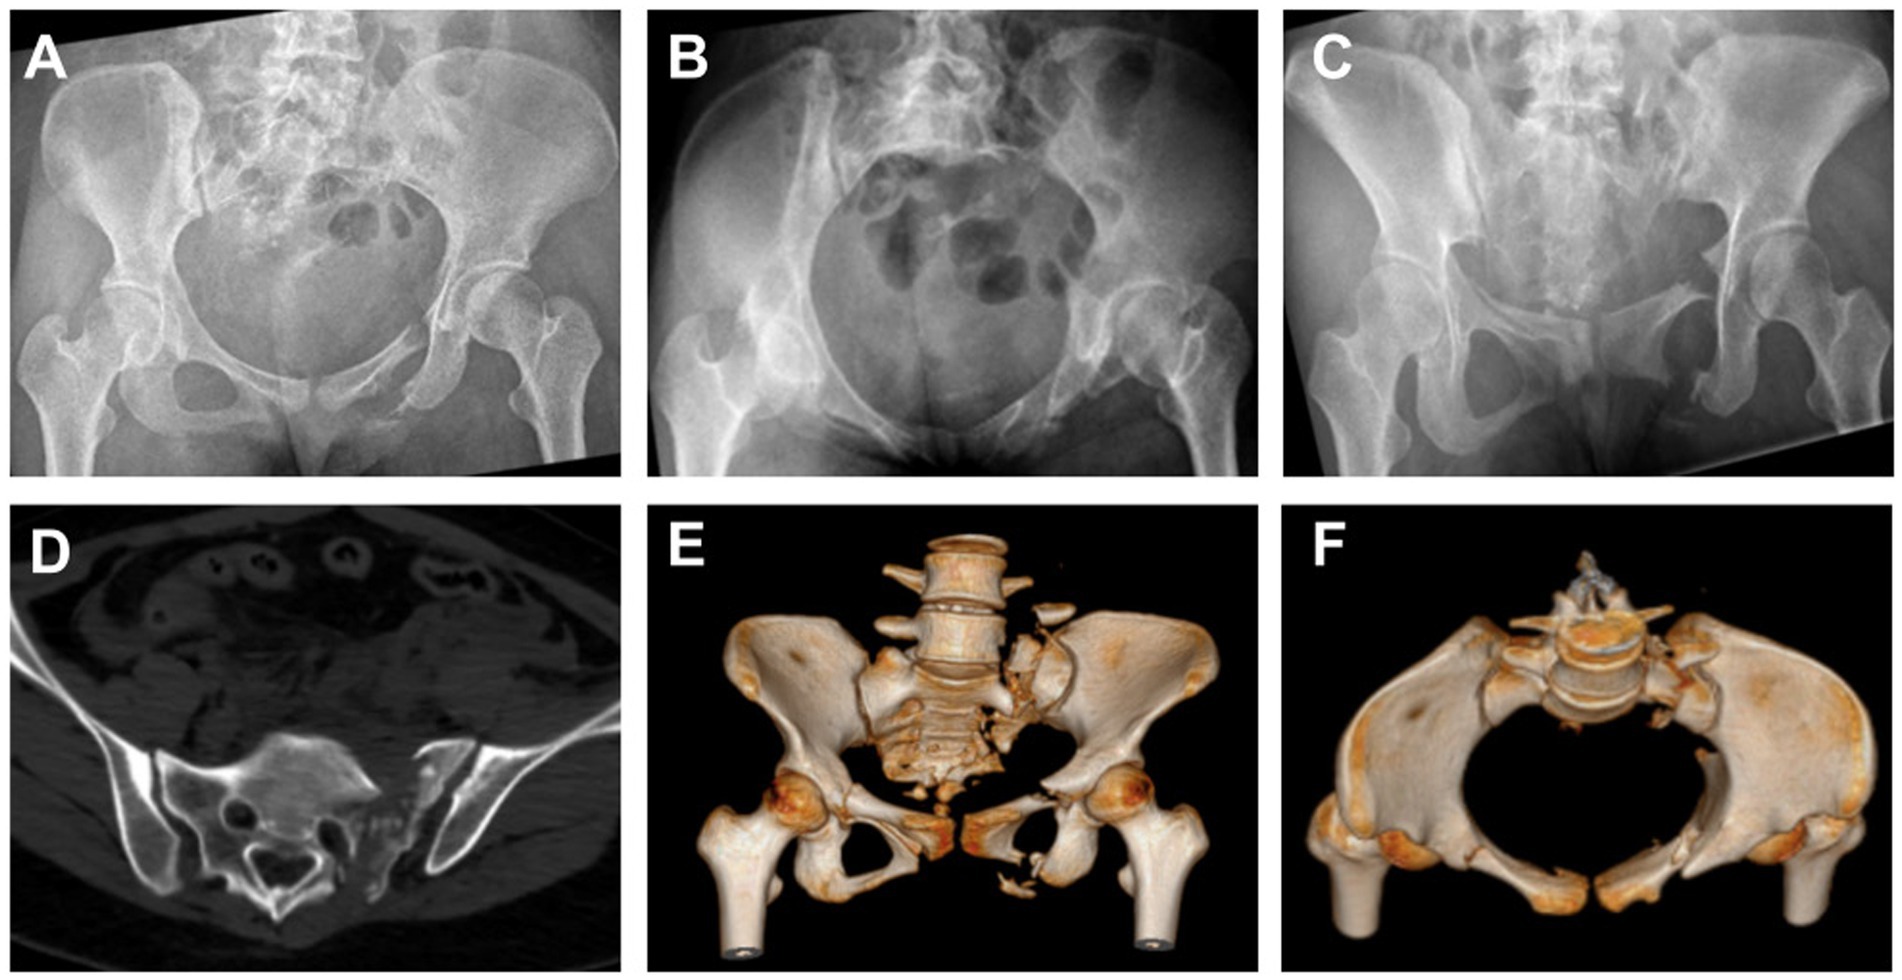

During the preoperative assessment, anteroposterior (AP), inlet, and outlet X-rays of the pelvis were obtained, along with CT scans for a comprehensive evaluation Figure 1. For patients with vertical instability, supracondylar femoral traction was applied. The surgical plan was developed by considering the fracture type, expected reduction outcome, and the feasibility of constructing bony tunnels.

Figure 1

Preoperative imaging studies of the patient’s pelvis were performed using X-rays in the anteroposterior (A), inlet (B), and outlet views (C). The findings suggested a fracture, and CT (D) with three-dimensional reconstruction (E,F) provided more detailed information.